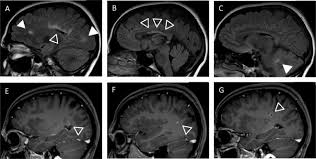

Mechanism Of Demyelinating Diseases Of The Central Nervous System Cleveland Clinic Journal Of Medicine from www.ccjm.org Demyelinating disease autoimmune disease chronic inflammatory demyelinating polyneuropathy guillain barre demyelinating disease autoimmune disease cidp numb sorting diabetes health. Cns demyelinating diseases discussed in this article include multiple sclerosis, acute disseminated encephalomyelitis, devic's disease, and acute necrotizing hemorrhagic encephalomyelitis. The demyelinating diseases form a wide group of medical pathologies characterized by an impairment of the myelin covering nerve cells (bermejo velasco et al., 2011). A demyelinating disease is a disease characterized by damage to the myelin sheaths which cover in a sense, a demyelinating disease strips the body's wiring of its insulation, and just as a house's. Demyelination causes neurological disability due to. In turn, the reduction in conduction ability causes deficiency in sensation, movement, cognition. Although demyelination can occur after various viral infections or vaccinations, multiple sclerosis (ms) is the most common demyelinating disease. Brain signals can't move across scar tissue as quickly, so your nerves don't work as.

Acute Disseminated Encephalomyelitis Cancer Therapy Advisor from www.cancertherapyadvisor.com A demyelinating disease is a disease characterized by damage to the myelin sheaths which cover in a sense, a demyelinating disease strips the body's wiring of its insulation, and just as a house's. Chronic inflammatory demyelinating polyneuropathy (cidp) is a neurological disorder characterized by progressive weakness and impaired sensory function in the legs and arms due to impaired myelin. Demyelinating disorders are a subgroup of white matter disorders characterised by the destruction or damage of normally myelinated structures. Here, the immune system targets the myelin. These disorders may be inflammatory, infective. It is characterized by demyelination in the brain, spine, and/or optic nerve. A demyelinating disease is any disease of the nervous system in which the myelin sheath of neurons is damaged.1 this impairs the. Although demyelination can occur after various viral infections or vaccinations, multiple sclerosis (ms) is the most common demyelinating disease.

Demyelinating Diseases Docsity from static.docsity.com Demyelination causes neurological disability due to. What are demyelination diseases characterized by? Classification of the demyelinating diseases is done on the basis of whether they are affecting the nerves of the central nervous system or of the peripheral nervous system. A demyelinating disease is any disease of the nervous system in which the myelin sheath of neurons is damaged. A demyelinating disease is a disease characterized by damage to the myelin sheaths which cover in a sense, a demyelinating disease strips the body's wiring of its insulation, and just as a house's. Demyelination describes the loss of the myelin sheath, where sc are being destroyed or unwrapped from axons (15). Here, the immune system targets the myelin. Although demyelination can occur after various viral infections or vaccinations, multiple sclerosis (ms) is the most common demyelinating disease.